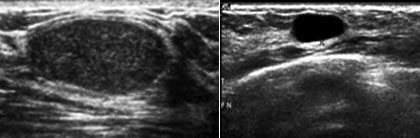

• Mamografiju i/ili ultrazvuk dojki

Šta je mamografija?

Mamografija je snimanje grudi sa niskom dozom rtg zracenja u cilju ranog otkrivanja karcinoma dojke koji je kod zena prvi po ucestalosti medju karcinomima. Preporucuje se uraditi je jednom godišnje, iza 40-te godine zivota, a ultrazvuk dojki do 40-te godine. Pregled takodjer treba uraditi ako osjetite tvrdo tkivo ili žlijezdu u grudima, iscjedak iz bradavice ili ako imate pozitivnu porodicnu anamnezu karcinoma dojke.

U 5-15% mamografskih snimaka naći ce se promjena koja zahtijeva dodatni pregled, kao ultrazvuk grudi, biopsiju ili kontrolnu mamografiju.